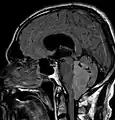

Épendymomes supratentoriels

Les épendymomes supratentoriels (SE) représentent entre 40% et 60% des tumeurs intracrâniennes. Localisées au niveau supratentoriel, ces tumeurs apparaissent comme des grosseurs peu homogènes, présentant des zones kystiques, des calcifications mais également des zones hémorragiques et nécrosées.

Aspect radiologique à l’IRM en séquence T1 après injection de Gadolinium d’un épendymome supratentoriel, caractérisé par une lésion bien délimitée du lobe frontal gauche avec prise de contraste hétérogène et des zones de nécrose.